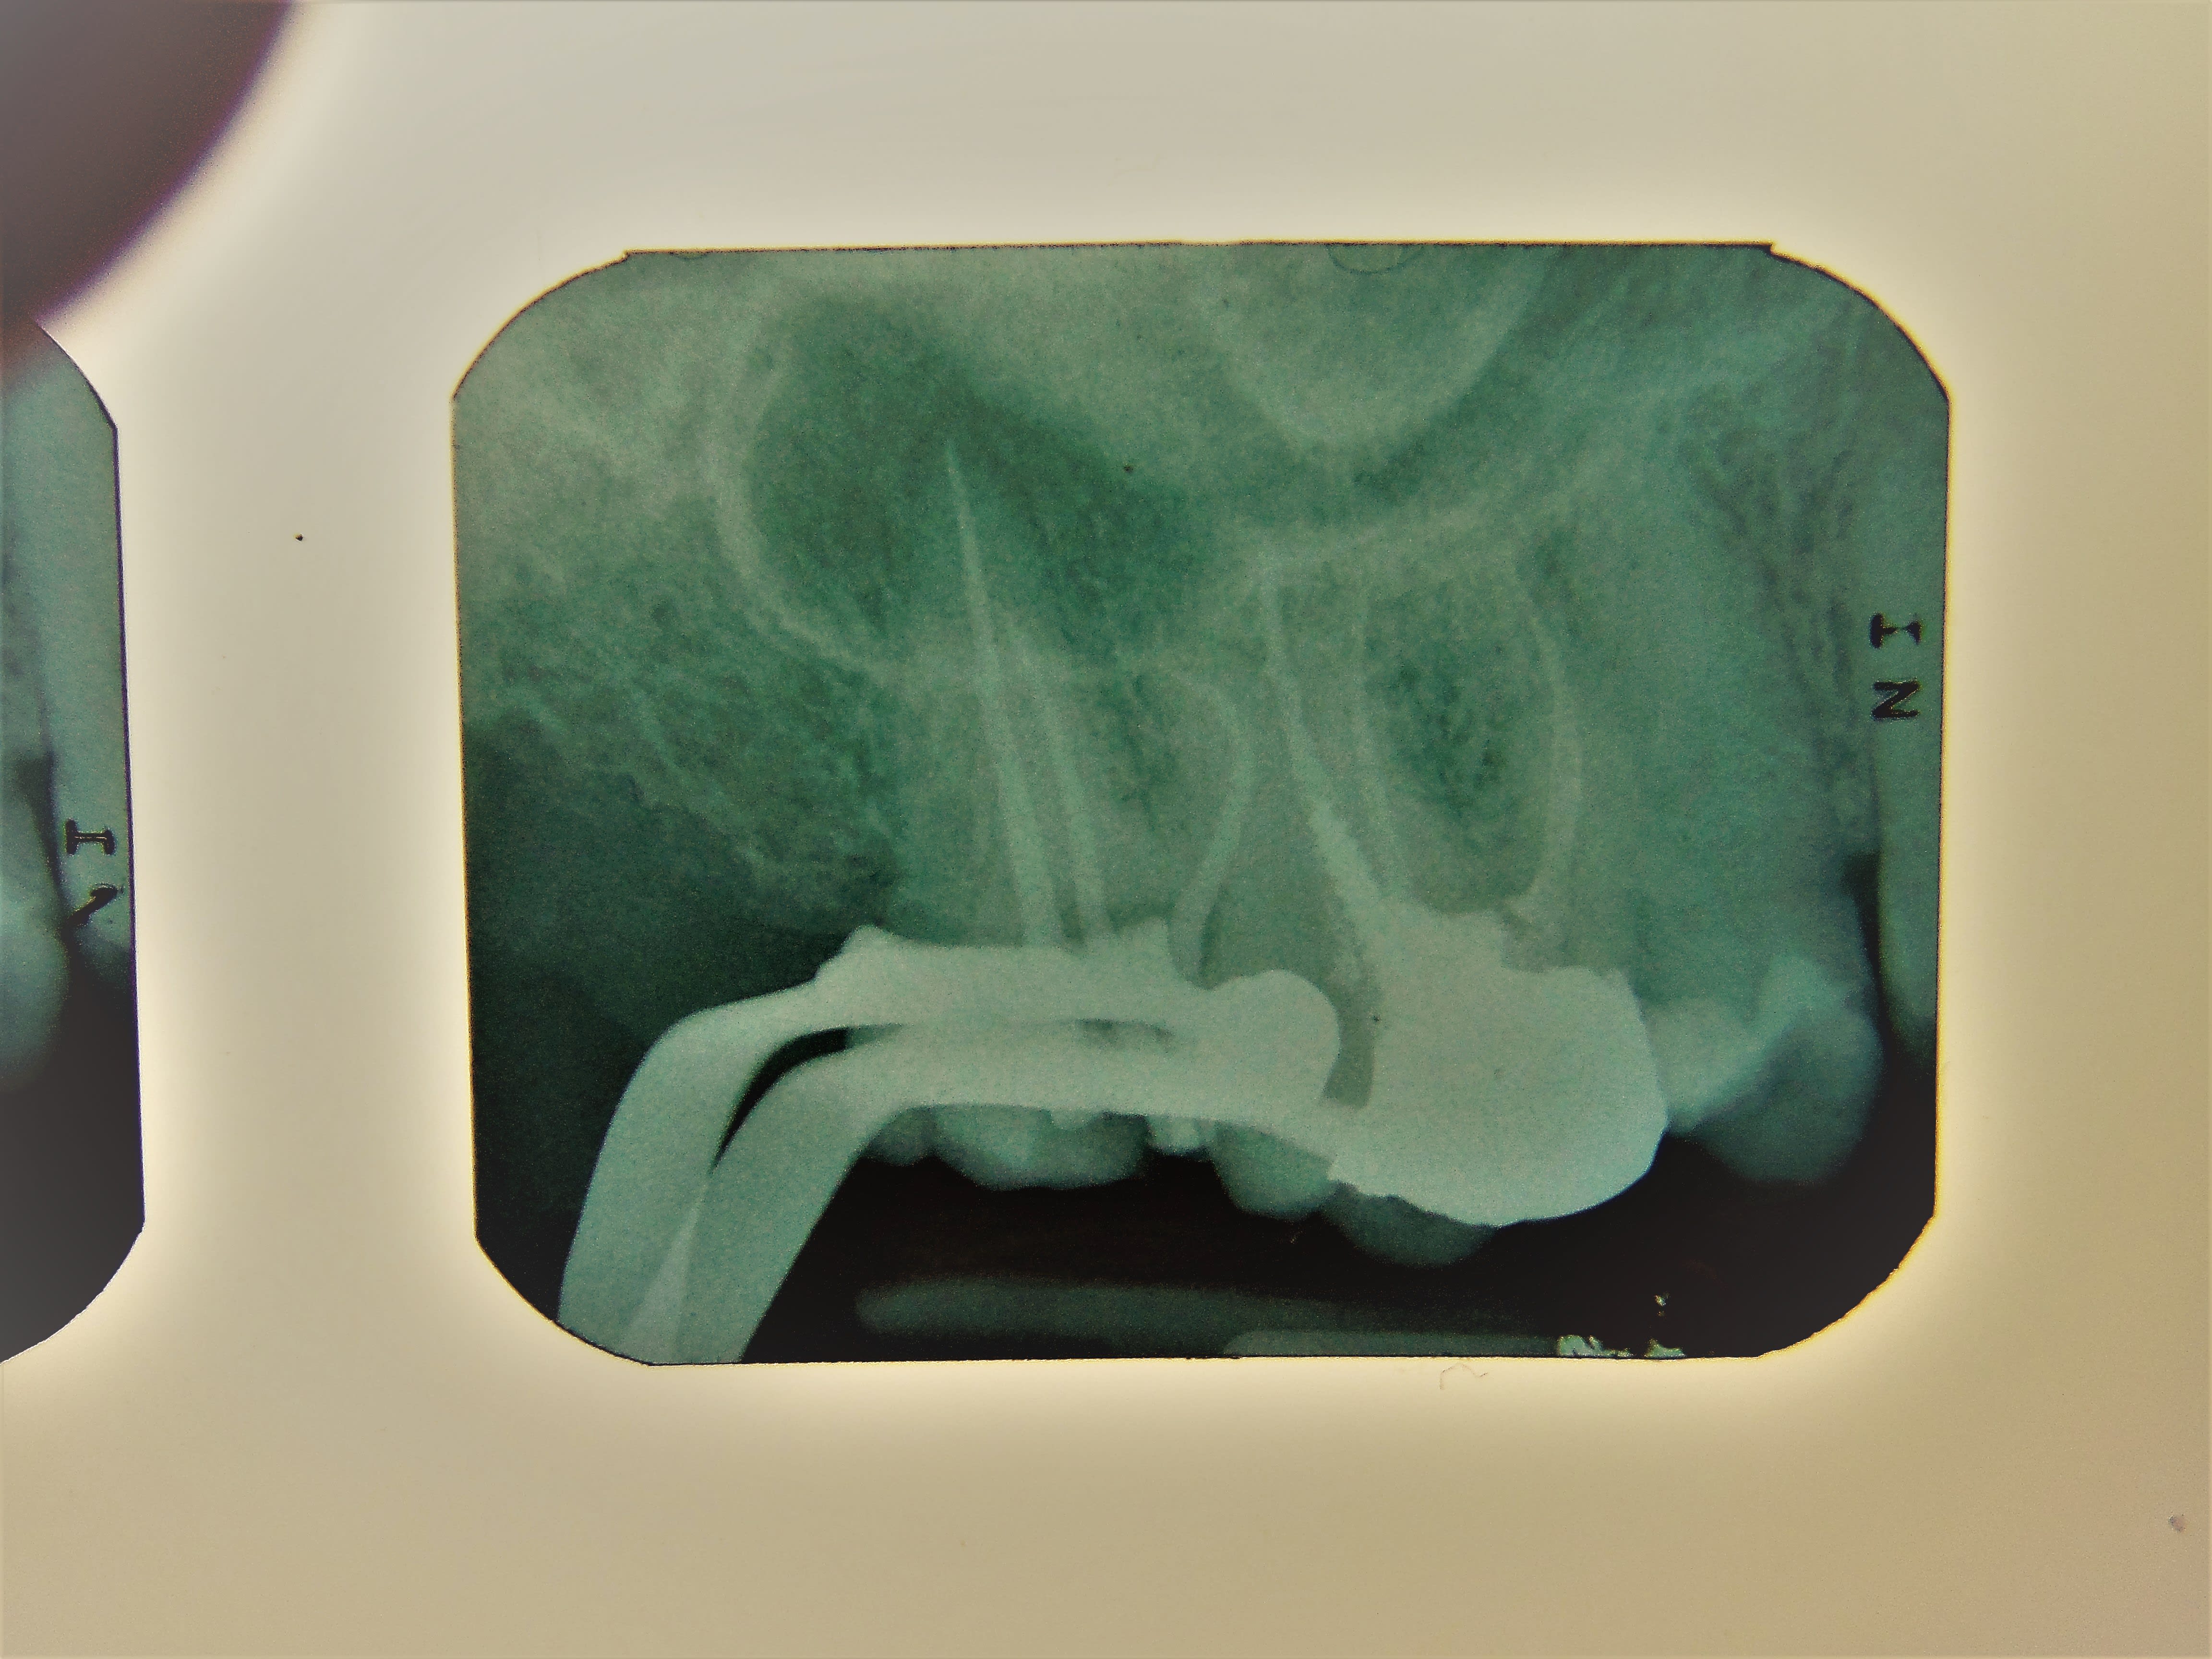

D2

Collection personnelle, y a pas que la complète dans la vie!

Dscf3035 3 hgezjz - Eugenol